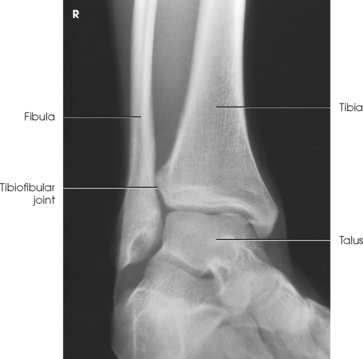

Structures shown: The image shows a true AP projection of the ankle joint, the distal ends of the tibia and fibula, and the proximal portion of the talus.

NOTE: The inferior tibiofibular articulation and the talofibular articulation are not “open” or shown in profile in the true AP projection. This is a positive sign for the radiologist because it indicates that the patient has no ruptured ligaments or other type of separations. For this reason, it is important that the position of the ankle be anatomically “true” for the AP projection shown (Fig. 6-92).